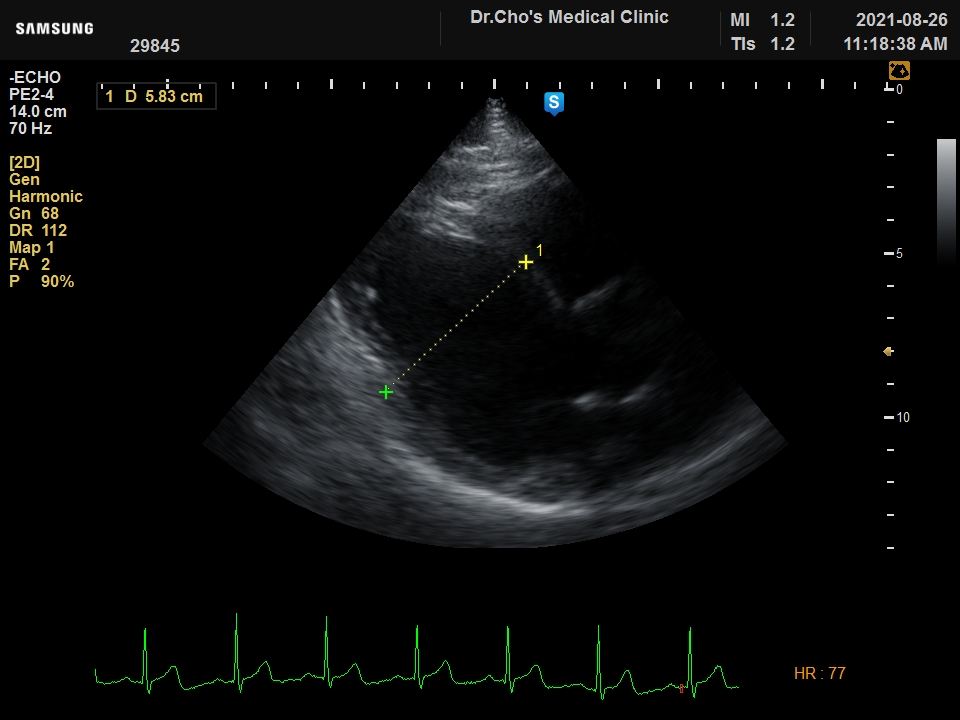

ÃÊÀ½ÆÄ°¶·¯¸®

¿ì½É½Ç °æ...